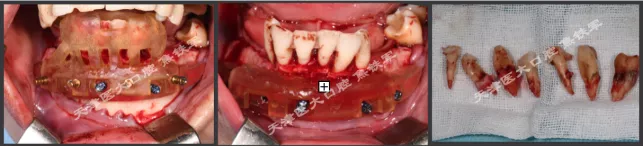

下颌即刻种植即刻修复手术过程

· 下颌士卓曼360数字化序列导板+预成临时修复体

· 翻瓣,利用松牙固定后的余留牙支持连接在一起的牙支持导板和基部导板,使骨支持的基部导板就位于骨面。

· 并用固位钉固定,拆除牙支持式导板,拔除余留牙。

· 基部导板上缘做为截骨线,精确去骨,平整骨面。

· 全程植入导板就位于基部导板上,固位钉固定,引导种植体植入。

· 种植体植入后,安装复合基台基底

· 临时修复体就位于基部导板,固位钉固定,口内Pick-up后取下修改,戴回口内,咬合关系良好。

上颌即刻种植即刻修复手术过程

· 上颌360数字化序列导板+预成临时修复体

· 拔除部分牙齿,翻瓣,利用剩余牙齿支持组合导板,辅助基部导板就位固定,基部导板上缘做为去骨线,精确去骨。

· 全程导板就位,引导种植体植入,安装复合基台。

· 种植体植入位置偏腭侧,唇侧骨量过于丰满,上颌骨前突,去骨修整骨边缘。

· 口内pick-up 固定临时修复体,患者上下颌咬合关系良好。